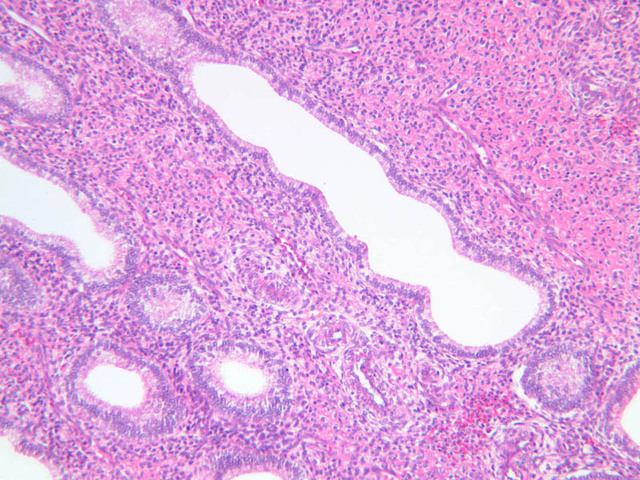

Secretory Phase

This phase occurs on days 15 to 27 and corresponds to the ovarian luteal phase characterized by rising levels of progesterone. The epithelial cells begin to secrete a mucoid fluid rich in nutrients, especially glycogen. The glands become highly coiled and folded and toward the end, very distended. The density of the stroma lessens as it becomes edematous. (slides B-99 [2.5x, 10x, 20x, 40x] [2.5x, 10x, 20x, 40x]; B-100 [1x, 2.5x] [2.5x, 10x, 20x, 40x] [2.5x, 10x, 20x, 40x])